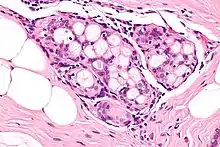

| Micrograph of collagenous spherulosis with the characteristic histomorphology - intratubular eosinophilic material with a spoke-like arrangement. H&E stain. | |

Collagenous spherulosis is characterized by a tubular/cribriform architecture with intratubular eosinophilic material that classically is arranged like the spokes of a wheel ("radial spikes"). There is usually no mitotic activity, and two cells populations (epithelial & myoepithelial) are present, like in benign breast glands.

The lesions are typically small (less than 50 spherules per lesion, less than 100 micrometers in size) and may be multifocal.